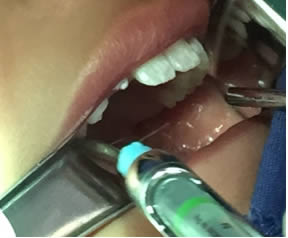

• Se realizó prueba para ratificar la proyección lingual la cual fue exitosa (Figura 10).

Figura 10. Prueba exitosa de tracción lingual

• Se irrigó bien la zona operatoria con solución fisiológica, se secó con gasa estéril, se revisó la hemostasia encontrándose en condiciones normales y se realizaron puntos simples de sutura utilizando Vicryl 3-0. Se terminó el acto quirúrgico sin accidentes ni incidentes. Figuras 11 y 12.

Figuras 11 y 12. Sutura y terminado del acto quirúrgico.